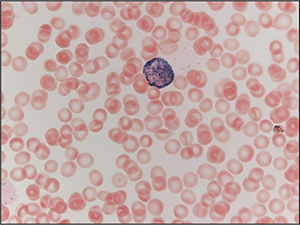

Two morphologic forms of APL are recognized including hypergranular (or typical) and microgranular variants. The blasts of typical APL have irregular large nuclei that can be bilobed and may have a “sliding plate” morphology. The cytoplasm is densely packed with large granules and occasional Auer rods. Microgranular variant blasts mostly have a bilobed morphology, and cytoplasmic granules are not apparent as they are submicroscopic. Cytochemical stains such as myeloperoxidase and Sudan black are strongly positive in both variants, often to the point that the cytoplasmic granules obscure the nucleus.

Case. A 16-year-old male presented with a one-week history of fatigue and easy bruising. Complete blood count revealed a white count of 4.8 × 103/mm3 with left shift of the myeloid lineage with 50 percent blasts, hematocrit of 31 percent, hemoglobin of 10.8 g/dL, and a platelet count of 29 × 103/mm3. Review of the peripheral blood smear showed numerous blasts with increased nuclear-cytoplasmic ratio and bilobed nuclei with sliding plate morphology (Fig. 2). Myeloperoxidase stain performed on the peripheral blood was strongly positive (Fig. 3). The morphologic and clinical findings were concerning for APL and thus the clinical team started ATRA (all-trans-retinoic acid) while awaiting final diagnosis. Flow cytometry revealed the blast population to be dim CD45, bright CD33, subset CD34, dim HLA-DR, dim CD13, CD117, subset CD56, and cytoplasmic MPO positive (Fig. 4). Dual color dual fusion fluorescence in situ hybridization was negative for t(15;17) (Fig. 5).6